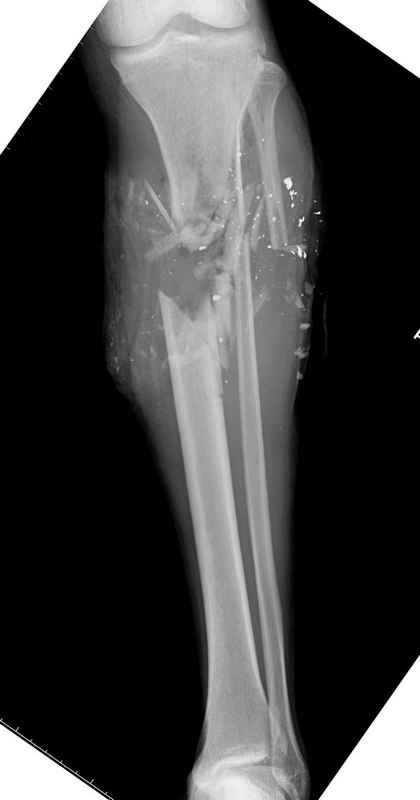

Здесь представлен больной 27 лет с ранениями, включая огнестрельный перелом большеберцовой кости.

14.08.09 повторная Irrigation&Debridment (чувстительственность из раны негативная) со сменой фиксации на медуллярный гвоздь и вакуумирование VAC

Имя     : 11 gsw tibila post IM nail.jpg

Тип     : image/jpeg

Размер  : 24313 байтов

Описание: отсутствует

Url     : http://weborto.net:8080/pipermail/ortho/attachments/20090831/f744a2dd/attachment-0023.jpg